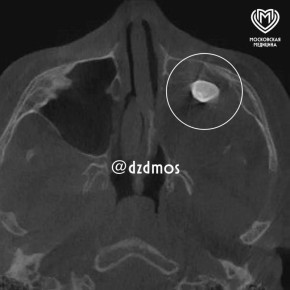

Врачи не удивились — они знали, что это. В московскую детскую больницу попал 15-летний мальчик, он жаловался на заложенный нос и асимметрию лица. Медики проверили его и нашли в гайморовой пазухе сформированный зуб. "Мальчику нужно было...